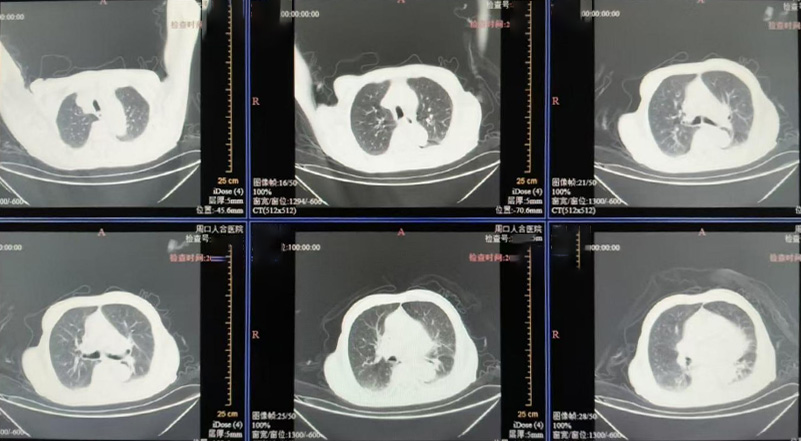

入院时患者已昏迷,生命体征极不稳定:血压显著偏低(休克状态),血氧明显下降,心率严重迟缓。检查提示:血钾显著升高(已达心脏骤停风险)、严重代谢性酸中毒、肾功能严重衰竭,感染及心功能指标严重异常。明确诊断为:尿毒症脑病、感染性休克、多脏器功能衰竭,病情危重至极,随时可能呼吸心跳骤停。

我院立即启动多学科会诊,重症医学科、肾内科、呼吸科、心内科、感染科等专家迅速集结。团队第一时间给予气管插管、呼吸机辅助通气、中心静脉置管、纤支镜吸痰、强效抗感染,并紧急启动床旁CRRT(连续性肾脏替代治疗),24小时清除血液毒素、纠正高钾血症和酸中毒,同时输血维持生命体征。

经过10天全力救治,患者病情显著好转:感染有效控制,心功能指标大幅下降;神志清醒,呼吸血压平稳,成功拔除气管插管、停用升压药;内环境逐步代偿,肾功能及电解质紊乱逐步纠正。患者已转入普通病房继续康复。